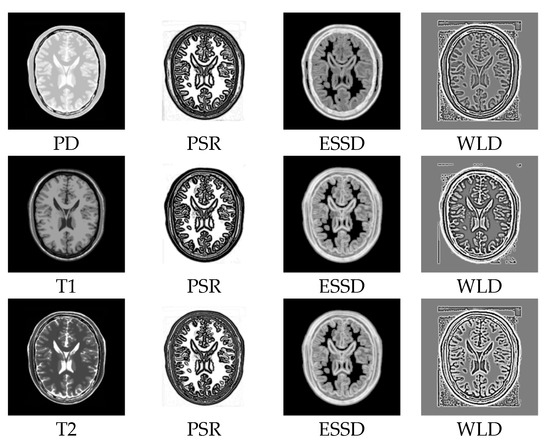

2.2. Structural Representation

3.2.1. Test on the BrainWeb Dataset